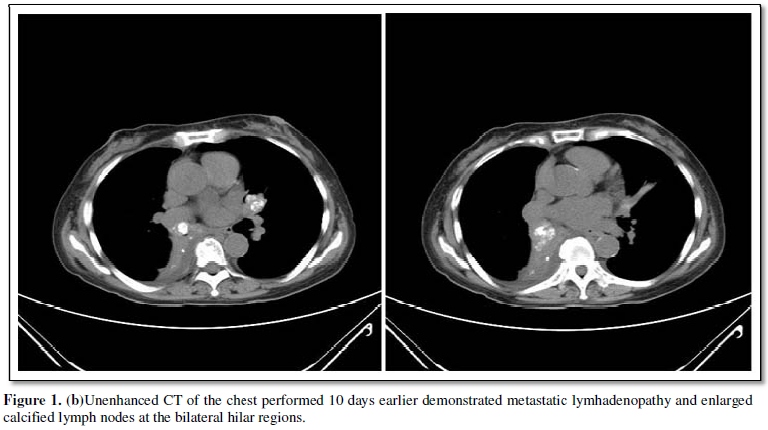

in bilateral pulmonary hilar regions (Figure 1a). Unenhanced CT of the chest

performed 10 days earlier demonstrated metastatic lymhadenopathy and enlarged

calcified lymph nodes at the bilateral hilar regions (Figure 1b). Postenhanced

CT demonstrated large metastases at the liver (Figure 1c). Although